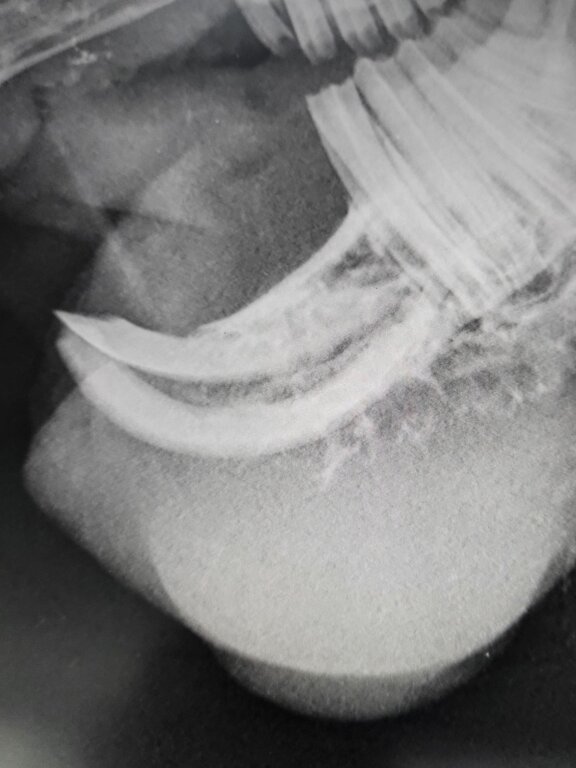

Bildgebende Verfahren:

In manchen Fällen können Röntgenaufnahmen oder Ultraschall helfen, die Ausdehnung des Tumors zu beurteilen und zu sehen, ob er bereits in andere Bereiche gestreut hat.